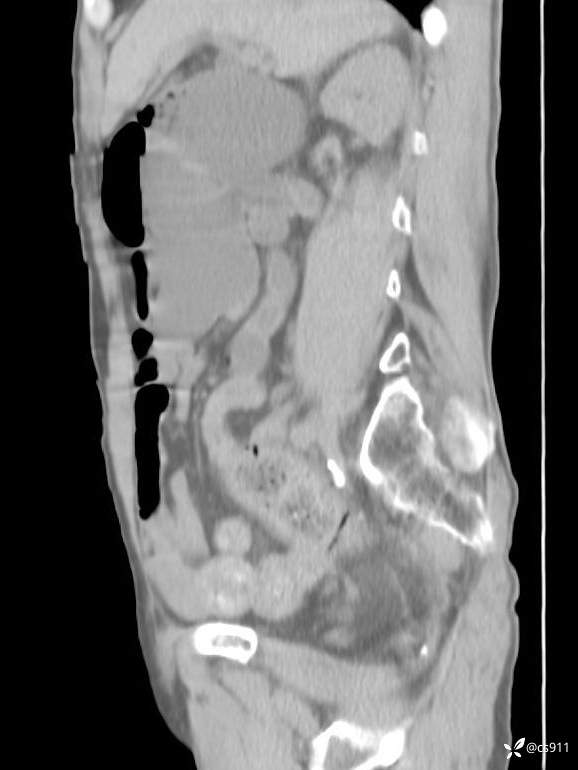

急腹症之急诊CT,原因?答案公布

男,77岁,腹痛、腹胀伴恶心呕吐1天。呕吐胃内容物,非喷射性呕吐,有咖啡色样胃内容物,诉有胃穿孔病史。查体:全腹平,下腹部压痛,全腹无反跳痛,叩诊呈浊音,移动性浊音阴性,肠鸣音减弱,1-2次/分。肛检:直肠未扪及明显肿物,可触及大量粪块。

T 36.6℃ P 80次/分 R 26次/分 BP 100/60mmHg

白细胞(WBC) H 14.55 10e9/L 4-10

红细胞(RBC) 4.58 10e12/L 4.3-5.8

中性粒细胞百分率(NEUT%) H 85.7 % 40-75

血淀粉酶(AMY) HH 1859 U/L 35-135

癌胚抗原(CEA) H 27.44 ng/ml 0-5

呕吐物 潜血试验 * 阳性 阴性

患者轮椅入室检查神志清楚, 能配合摆位和呼吸